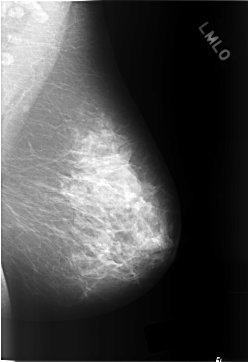

C_0304_1.LEFT_MLO

LEFT_MLO LINES 5792 PIXELS_PER_LINE 3968 BITS_PER_PIXEL 12 RESOLUTION 50 NON_OVERLAY